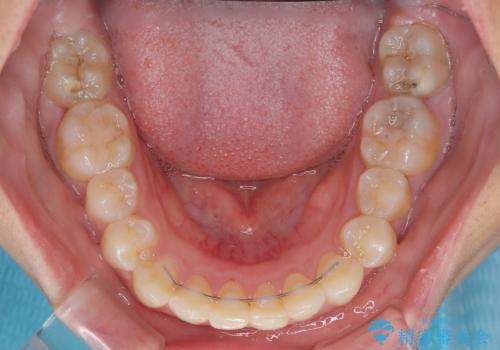

- 前歯のデコボコと歯肉に埋もれている奥歯を気にして来院された患者様です。

インビザラインでの治療を希望されていましたが、左右の下顎大臼歯が歯肉に埋もれており、特に右側は歯軸が顕著に傾斜していたため、インビザライン単独での治療は困難と判断し、ワイヤー装置を併用することとしました。

ワイヤー装置での下顎臼歯改善には時間がかかることが予想されたため、下顎のワイヤー矯正と並行して上顎をインビザラインで整え、その後インビザラインにより上下歯列を整える矯正治療を行うこととしました。

ワイヤー装置を併用したことで、レントゲン写真からも分かるとおり歯軸をしっかりと改善させることができました。